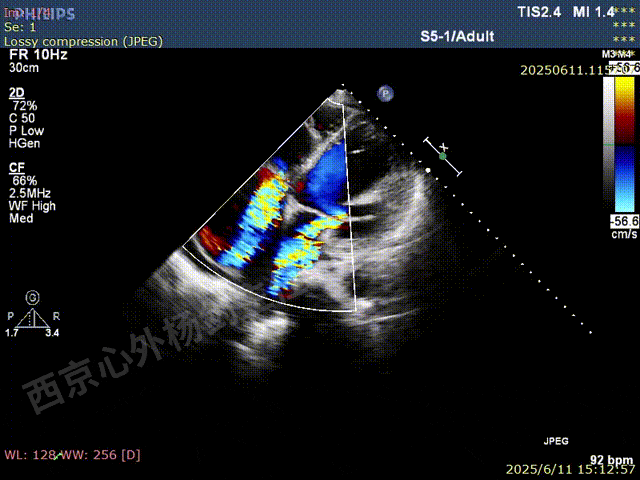

彩色血流示:二尖瓣反流缩流颈彩宽6.6mm,面积17cm²,容积30ml;二尖瓣瓣口面积6.6cm²,瓣环内径:左右径34mm,前后径34mm。2区瓣叶长度:前叶36mm,后叶20mm,叶环比1.6. 三尖反流面积17.2cm²,容积33ml,Vmax 291cm/s,PGmax 34mmHg。

二尖瓣后叶栓系严重,前叶相对错位,反流束沿2区分布广泛,2偏3区处存在反流。

反流宽度至少23mm,因影像调整困难,考虑实际反流更宽。